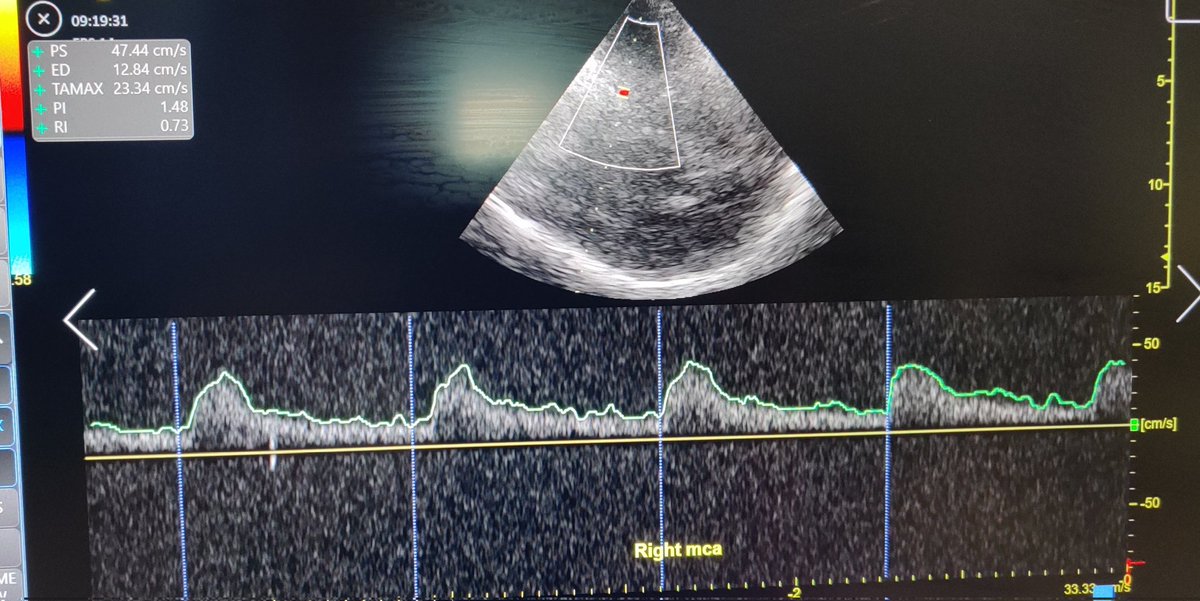

📖Transcranial ultrasound in the critically ill patient: a narrative review🧠 - The Past, Present and Future! 🔗 https://t.co/4Kcp0EptST

#TCD #TCCD #Ultrasound #IntensiveCare #CriticalCare #POCUS #NeuroPOCUS #FOAMed #NeuroICU #Neurosonology #Neuroultrasound

#POCUS #MedTwitter @yourICM @ICS_updates @CritcareLTHTR @Shashi_bc @shond3 #radiology Brain ultrasound- focused TCD with features of high ICP and poor perfusion. Confirmed on CT brain that showed devastating brain injury.